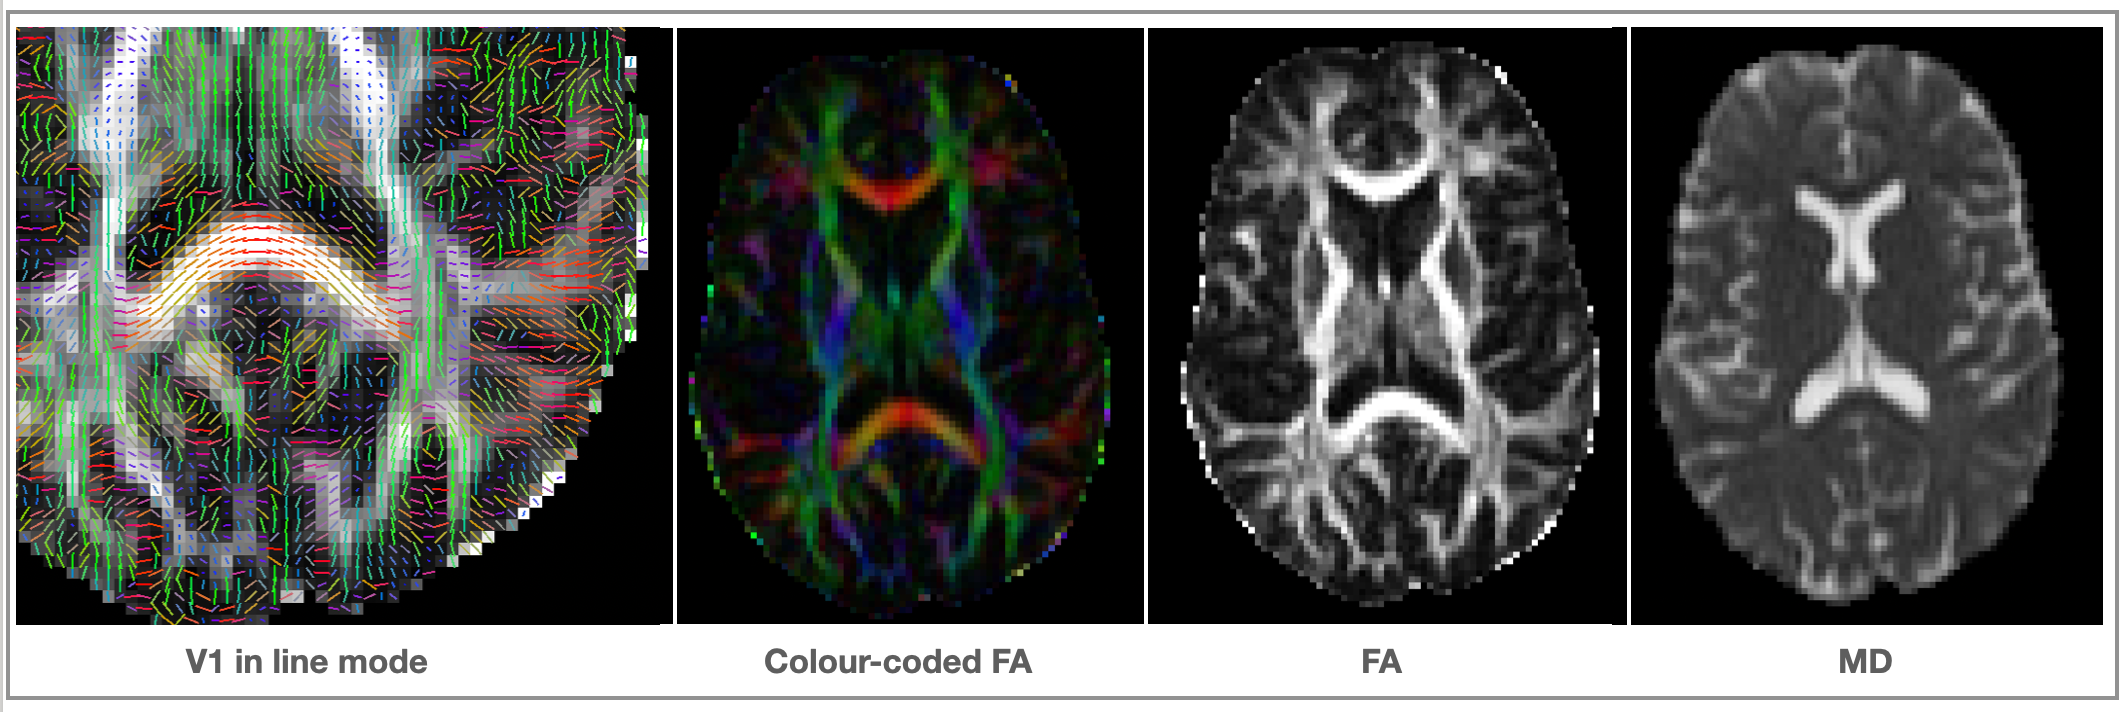

Outputs of dtifit

<basename>_V1- 1st eigenvector<basename>_V2- 2nd eigenvector<basename>_V3- 3rd eigenvector<basename>_L1- 1st eigenvalue<basename>_L2- 2nd eigenvalue<basename>_L3- 3rd eigenvalue<basename>_MD- mean diffusivity<basename>_FA- fractional anisotropy (isotropic ~ 0; stick-like ~1)<basename>_MO- mode of the anisotropy (oblate ~ -1; isotropic ~ 0; prolate ~ 1)<basename>_S0- raw T2 signal with no diffusion weighting

Optional output

<basename>_sse- Sum of squared error of diffusion tensor fit.<basename>_tensor- tensor as a 4D file in this order: Dxx, Dxy, Dxz, Dyy, Dyz, Dzz